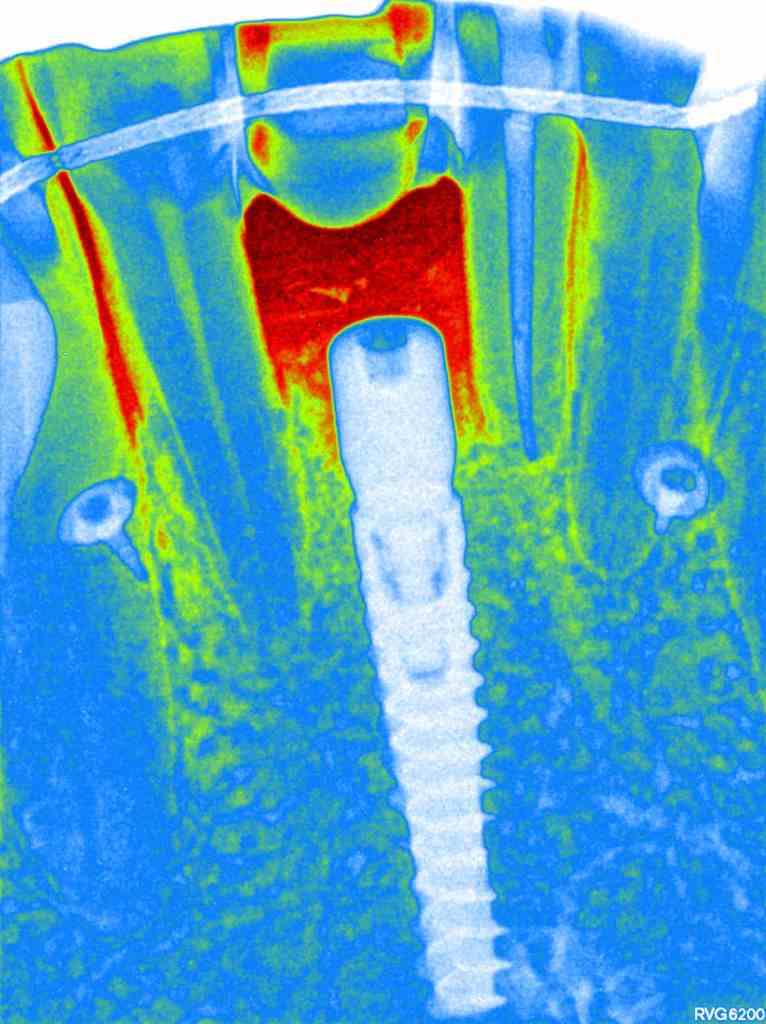

Una vez obtenida una adecuada regeneración ósea (Figuras 13-15), se procede a la colocación de un implante en la posición del 4.1, asegurando una correcta estabilidad primaria (Figuras 16-17).